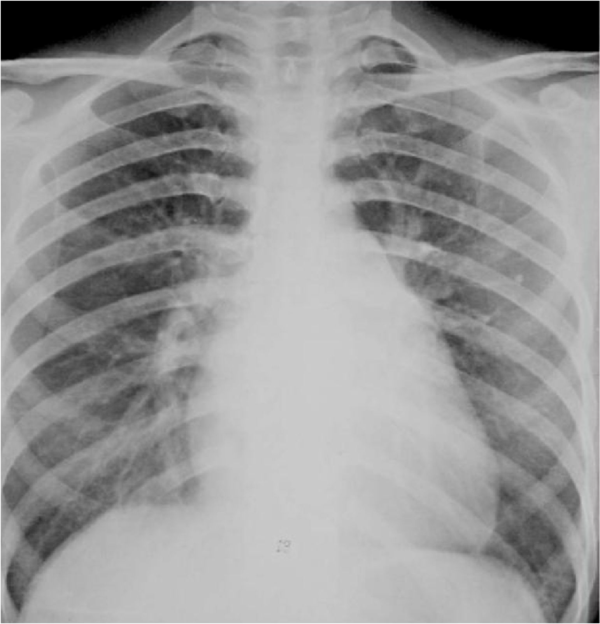

图2 胸片正位:梨形胸廓,心影增大

看图(扩张型心肌病,全心衰-心肌无力了)要么是心脏本身增大(心包积液